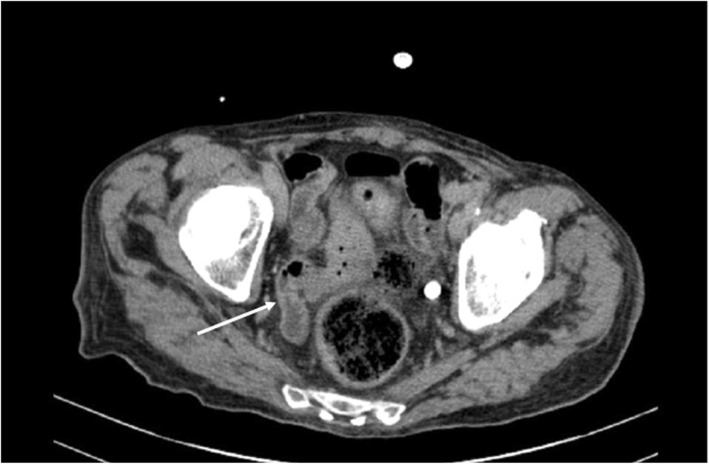

Three months after treatment completion, the patient developed persistent fever and severe weight loss. Laboratory and radiological investigations excluded bacterial infections and extranodal lymphoma localizations. An abdominal CT scan showed parietal thickening of the ileo-caecal region (Fig. 1), and endoscopy revealed mucosal ulcers of both the oesophagus and the colon. Biopsies yielded CMV intracytoplasmic inclusions. HIV antibody testing was negative.

Fig. 1.

Abdominal CT scan. The arrow shows parietal thickening of the ileo-caecal region